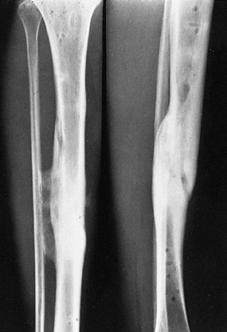

![]() |

Figure 133.1.

Anteroposterior roentgenograms of a 46-year-old man with chronic osteomyelitis. The patient was treated with debridement followed by insertion of aminoglycoside-impregnated methylmethacrylate beads and a local muscle flap. |